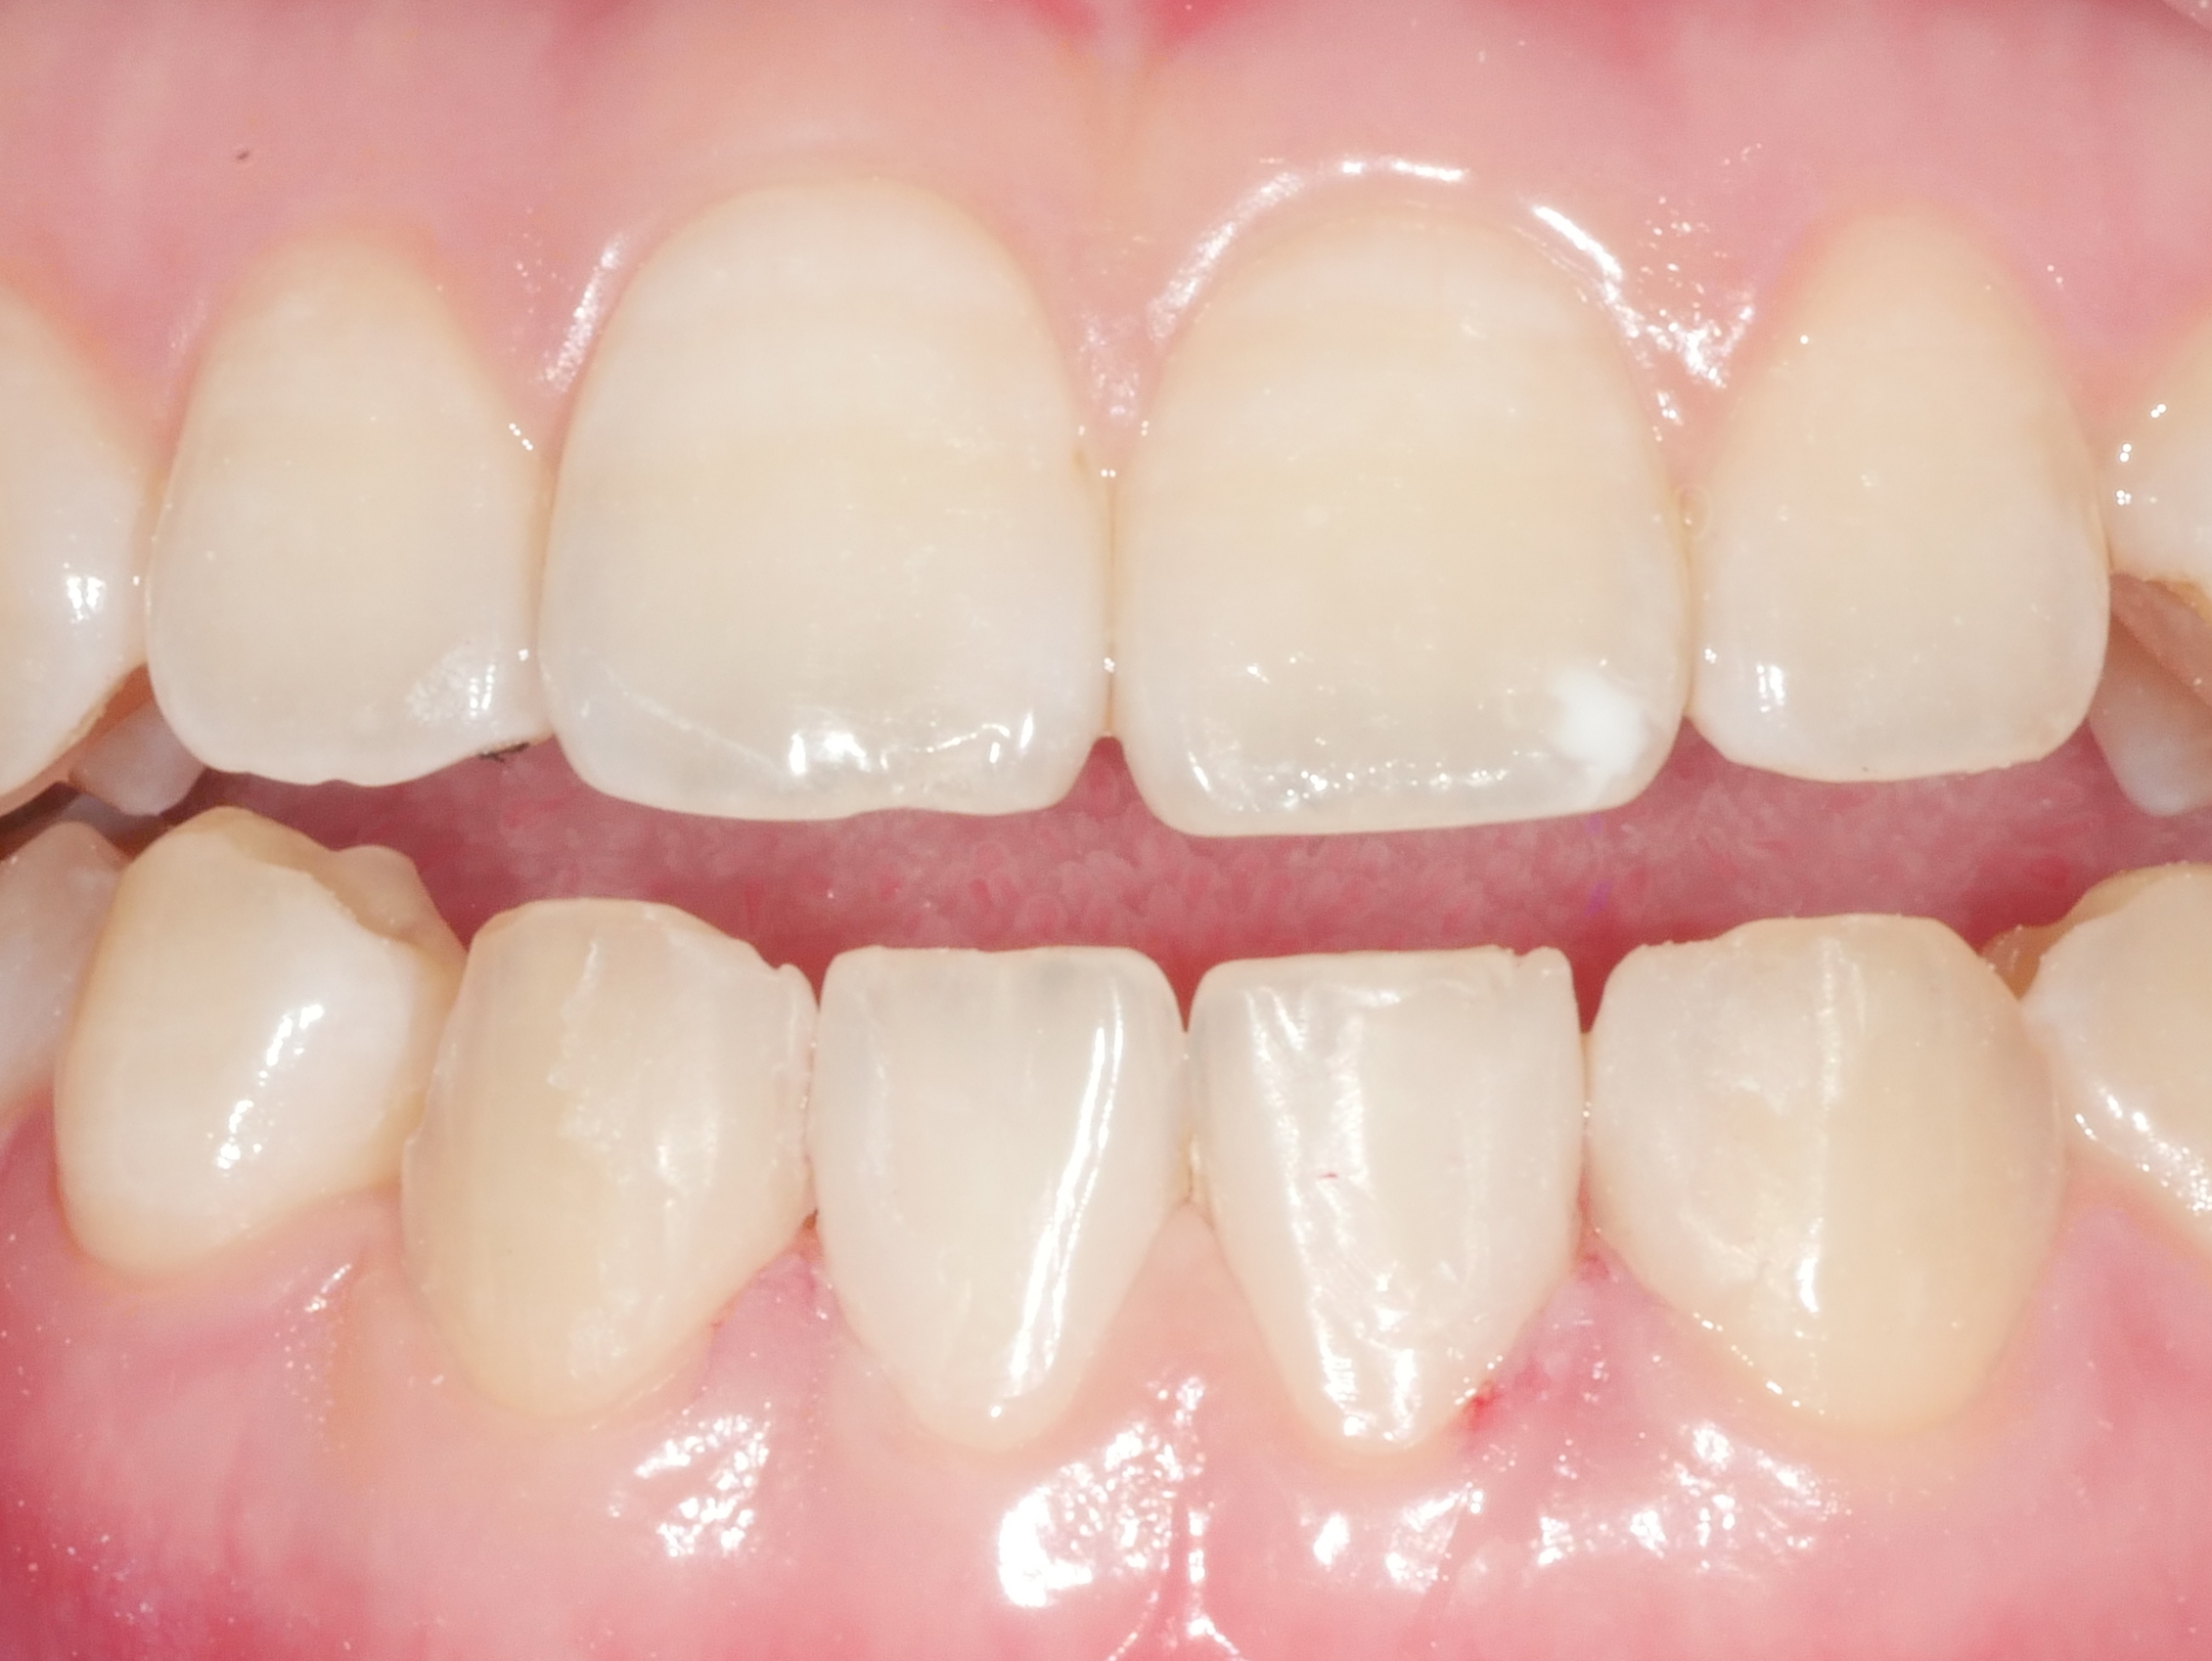

CASE.01 아래 앞니 치아 벌어짐 치료

• 아래 앞니 치아 벌어짐 치료

내원 당일 치아 삭제 없이 레진치료

치료전/후 2024.05.07